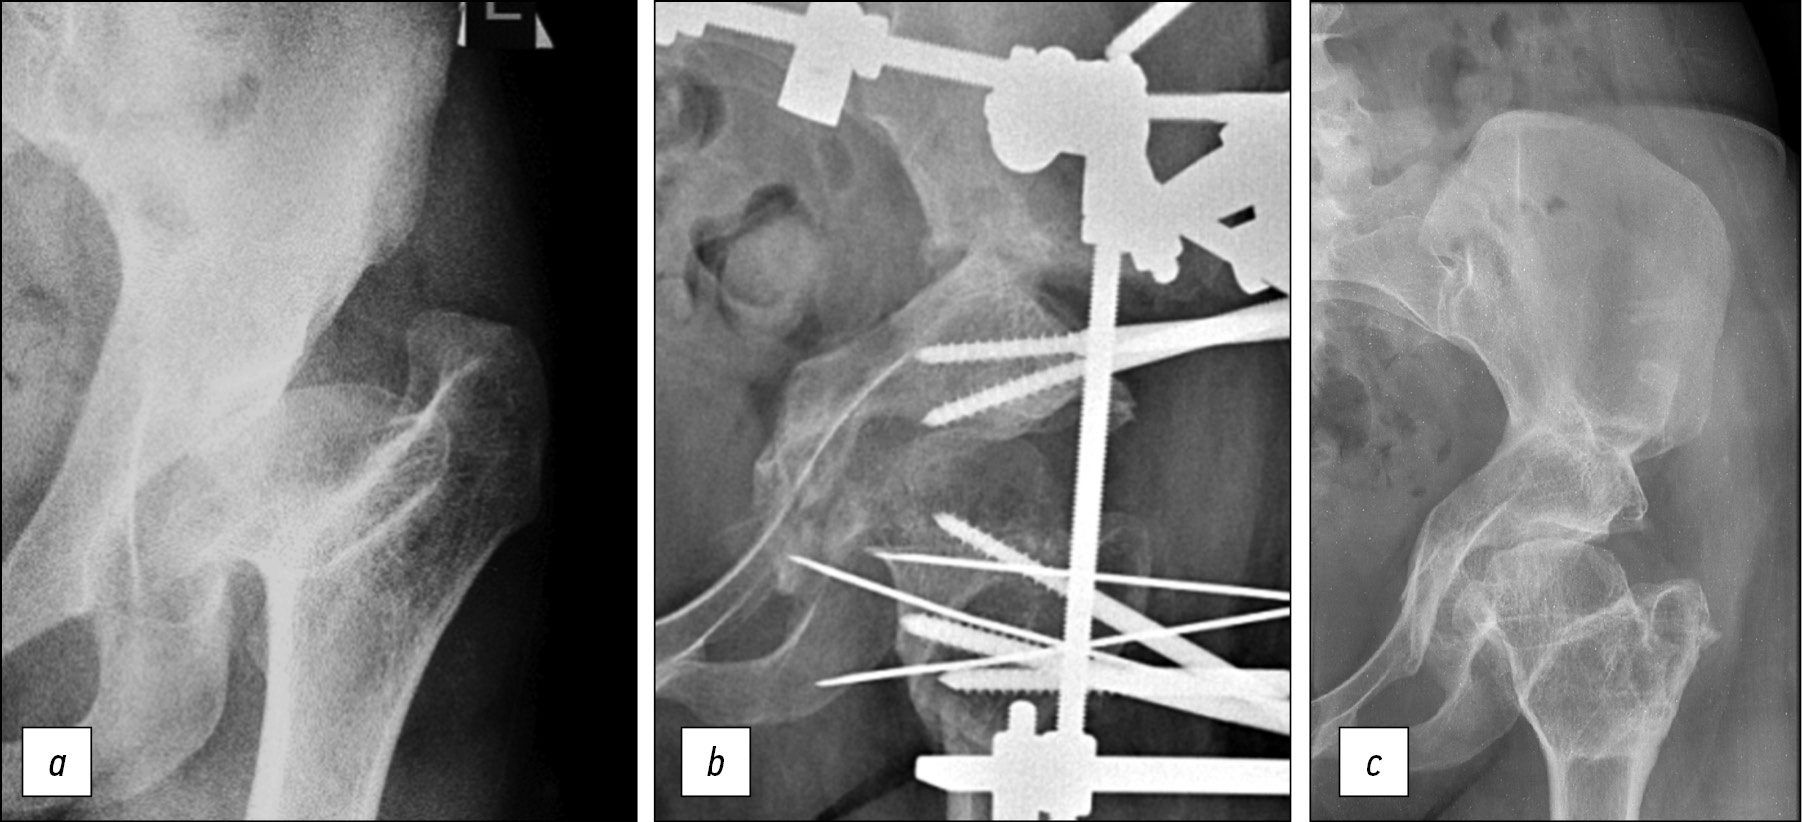

Рис. 1. Рентгенограммы пациентки 25 лет: a — до лечения: диспластический коксартроз II степени, ишемическая деформация проксимального отдела бедра вследствие асептического некроза головки при лечении врождённой дисплазии тазобедренного сустава (ISH 1,15, ATD –18 мм), остаточная дисплазия вертлужной впадины (WBZ 32°), децентрация головки левого бедра (ICAS 0,97, AHI 0,5); b — в процессе лечения: остеотомия таза, двойная чрезвертельная остеотомия бедра; c — через 5 лет: ATD 10 мм, WBZ 0°, AHI 0,95

Fig. 1. Radiographs of a 25-year-old patient: a — before treatment: dysplastic coxarthrosis of degree II, ischemic deformation of the proximal femur due to avascular necrosis of the head during the treatment of congenital dysplasia of the hip joint (ISH 1.15, ATD –18 mm), residual dysplasia of the acetabulum (WBZ 32°), decentration of the head of the left femur (ICAS 0.97, AHI 0.5); b — during treatment: pelvic osteotomy, double transtrochanteric osteotomy of the femur; c — after 5 years: ATD 10 mm, WBZ 0°, AHI 0,95